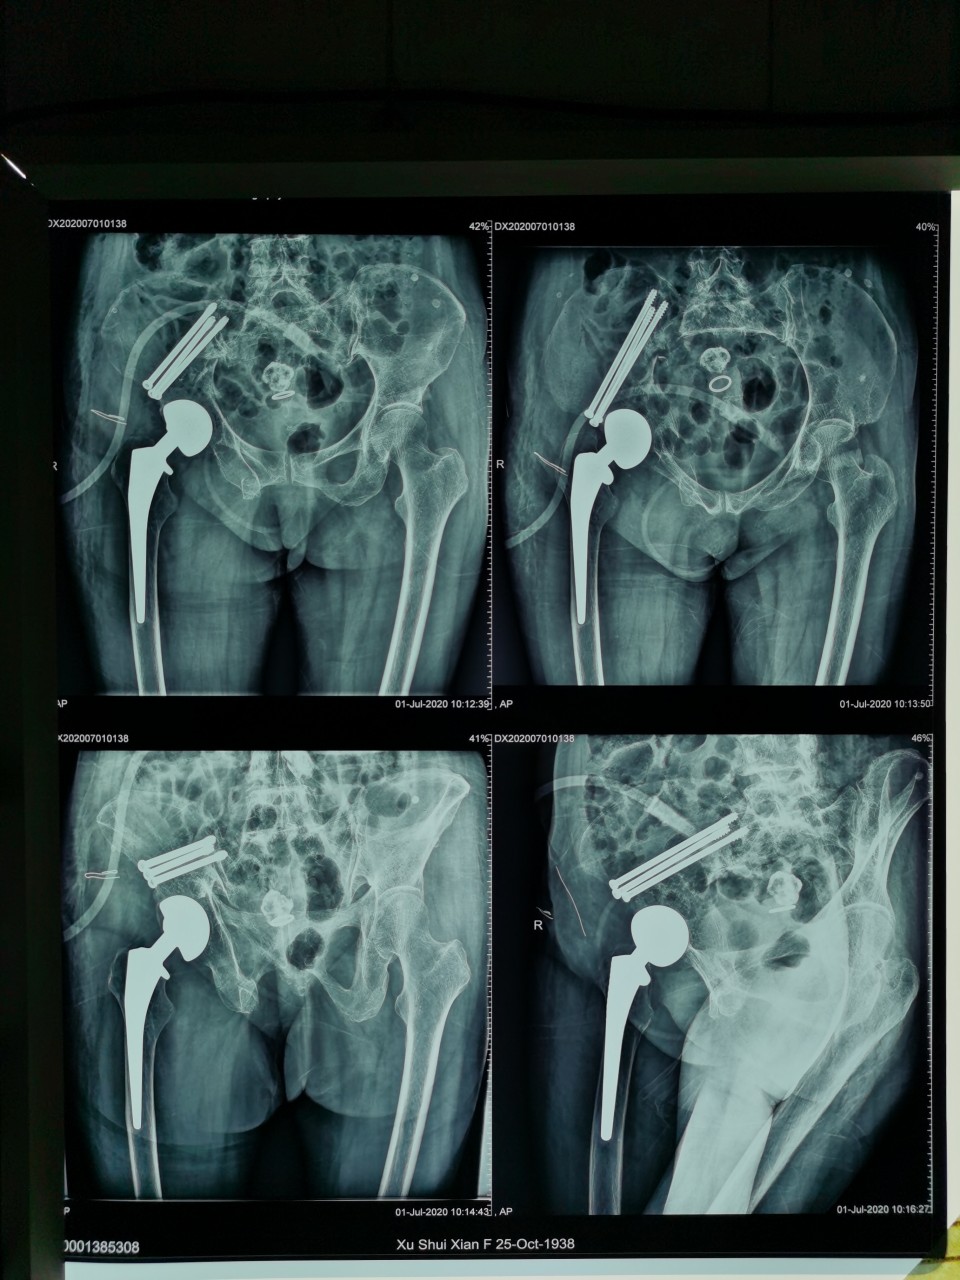

术后

患者女,81岁,既往曾因股骨颈骨折行右髋关节置换术,此次入院当天因外伤致髋部周围疼痛及活动受限入住我院创伤骨科。经术前检查及评估,诊断为“骨盆骨折”。对于此例高龄骨盆骨折患者,王刚副主任医师团队决定为其施行“闭合复位微创内固定手术”,手术用时仅30分钟,在闭合复位后,通过3枚骨盆通道螺钉固定骨折部位,基本无手术出血,术后两天患者恢复良好,予以出院。